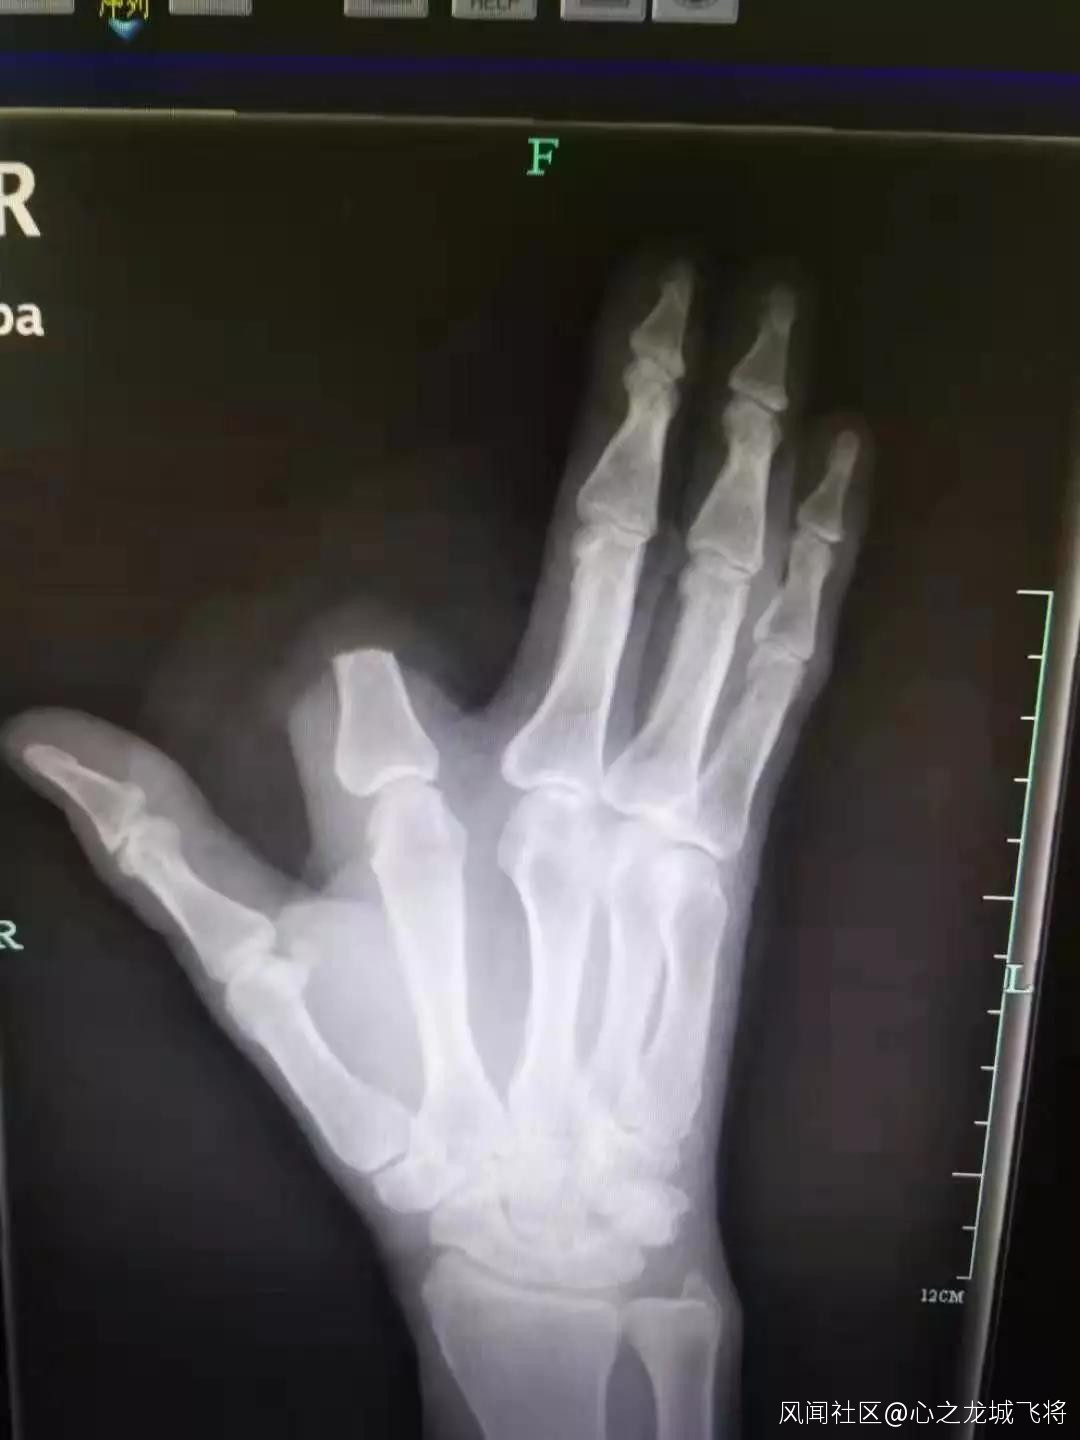

4小時前,他在山上幹活時,食指被毒蛇咬了一口。“打開一看,我們發現患者的食指少了一大截。”袁丞達一問,張先生顫抖着回答,“砍了,保命要緊!”

事後,他將斷指就地丟棄,沒有一併帶到醫院。檢查結果出來,張先生的凝血功能正常,醫生為他注射了抗蛇毒血清。本來,斷指尚可以再植,如今,只能由骨科醫生手術處理斷指殘端,張先生也將留下終身殘疾。